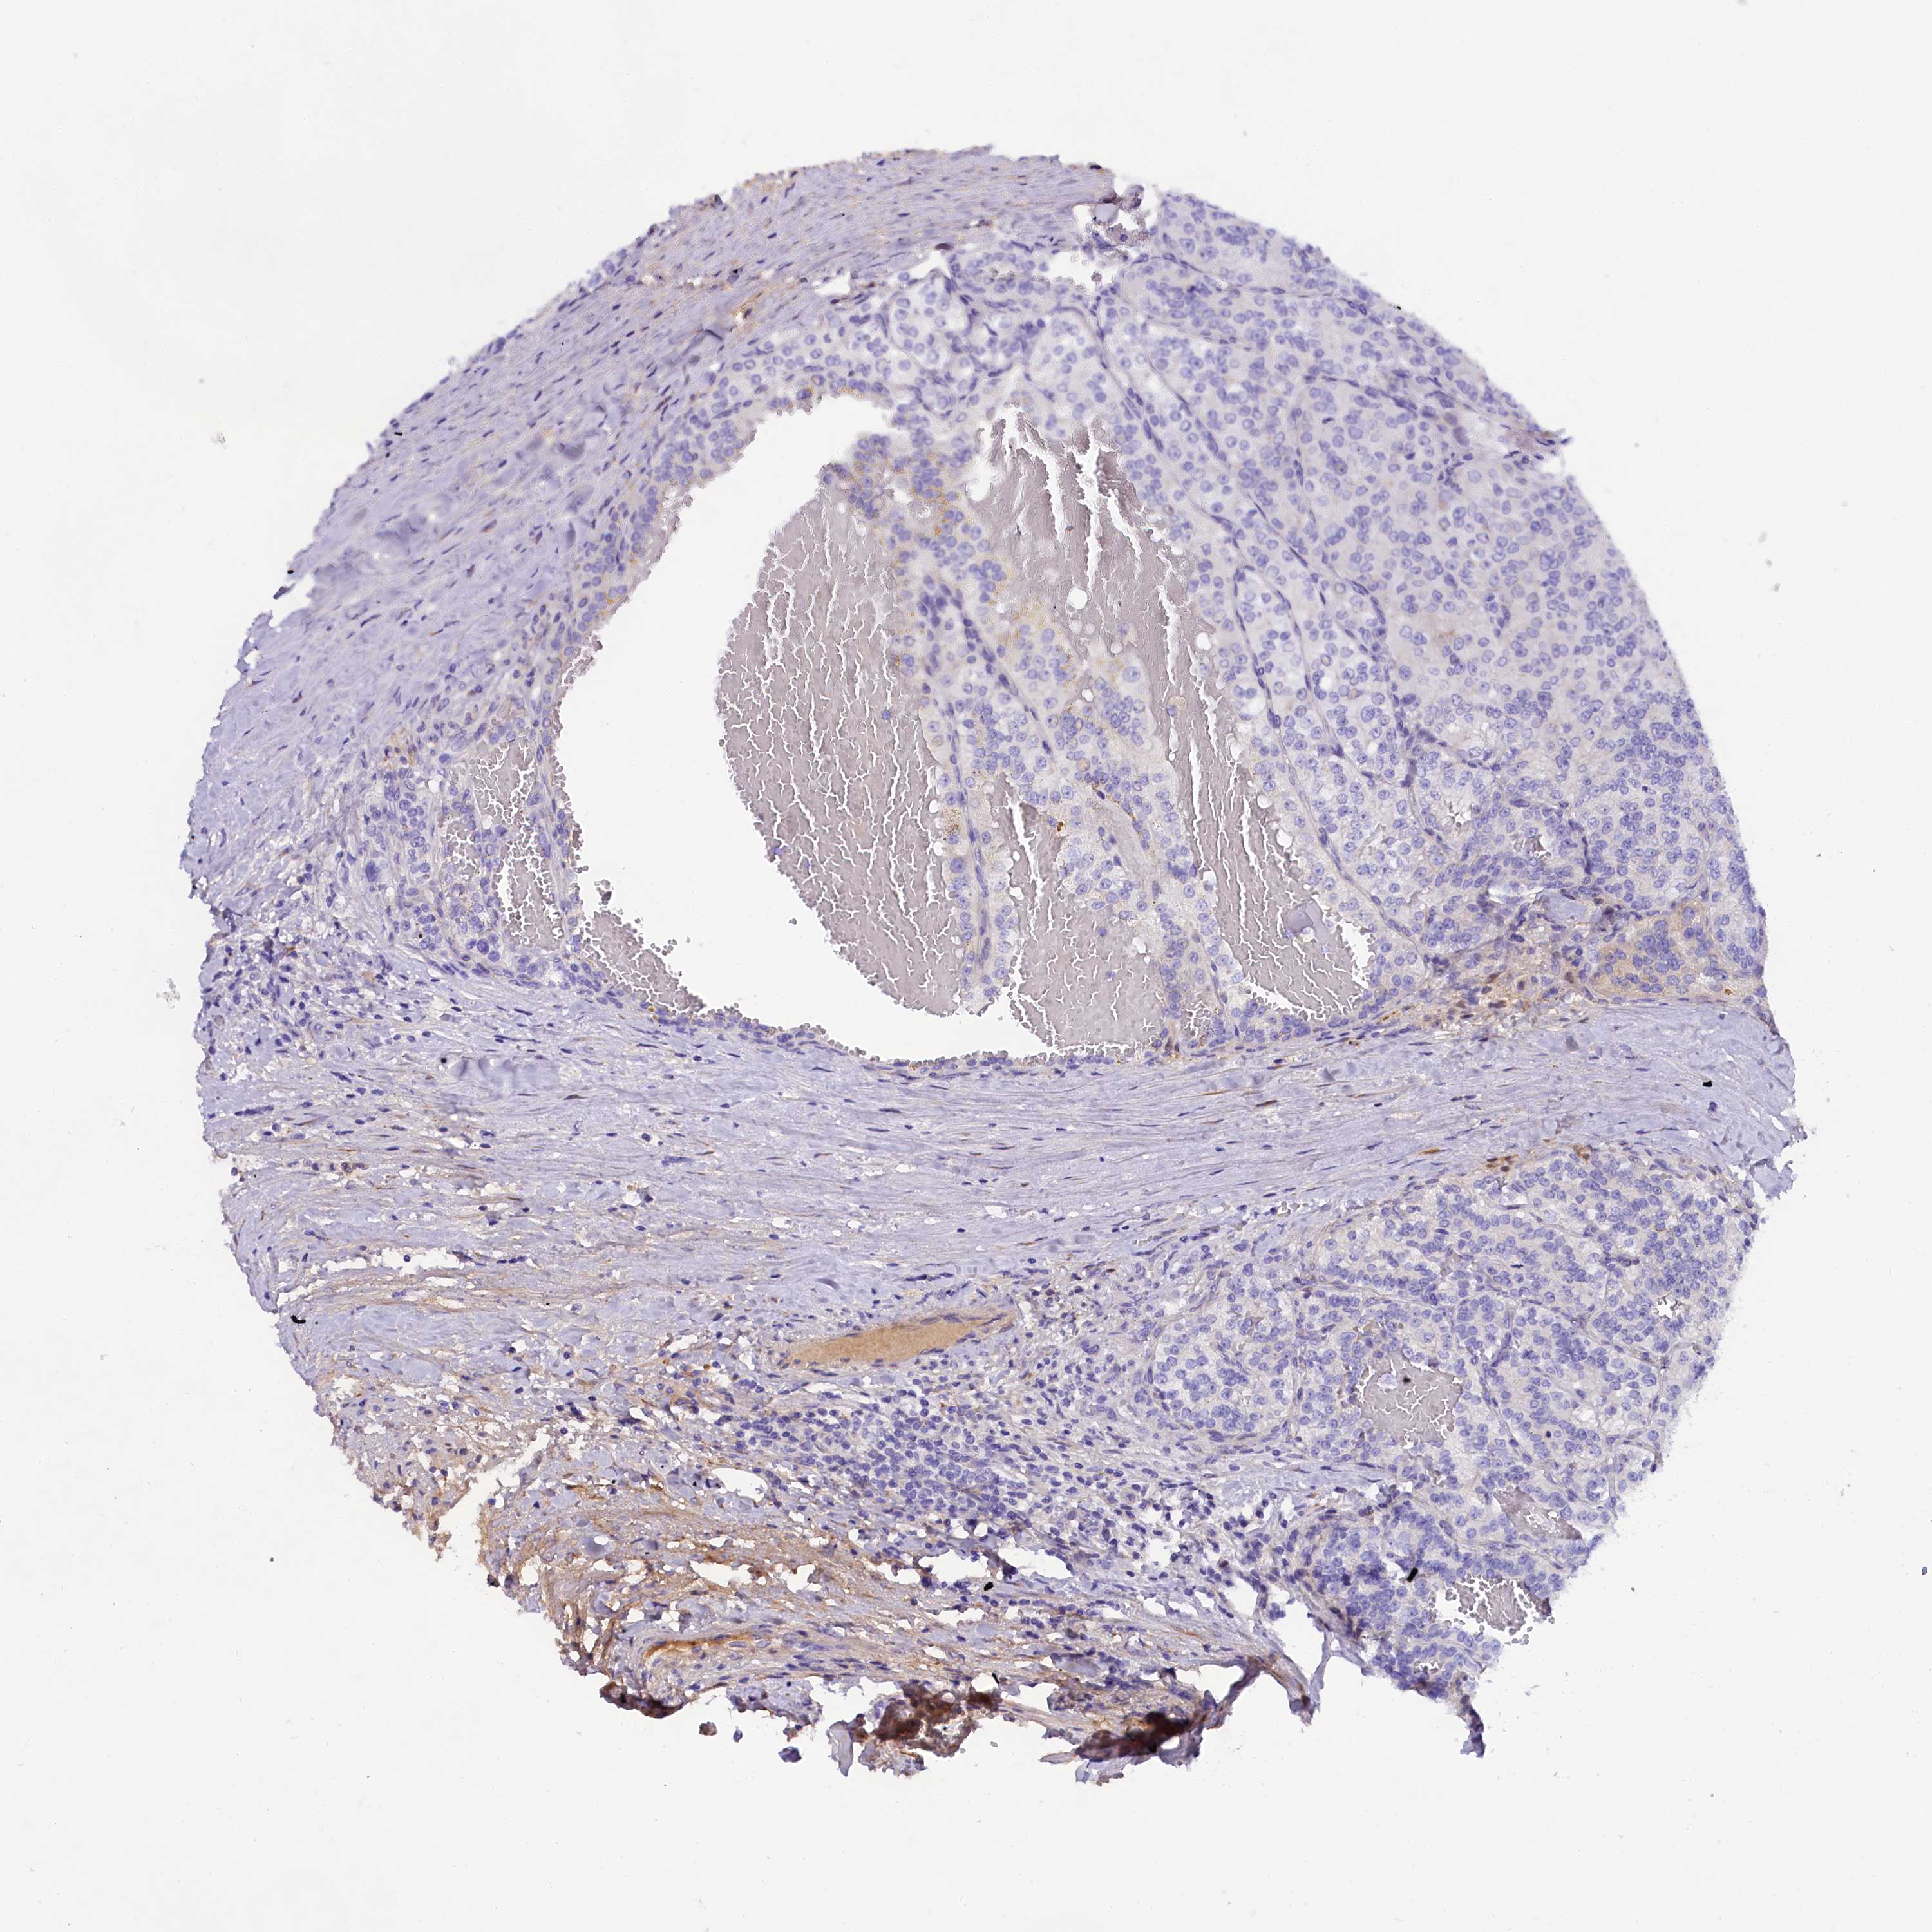

SOD3

CANCER RENAL CANCER Show tissue menu

KICH TCGA KIRC TCGA KIRC VALIDATION KIRP TCGA PROTEIN RCC CPTAC PROTEIN EXPRESSION